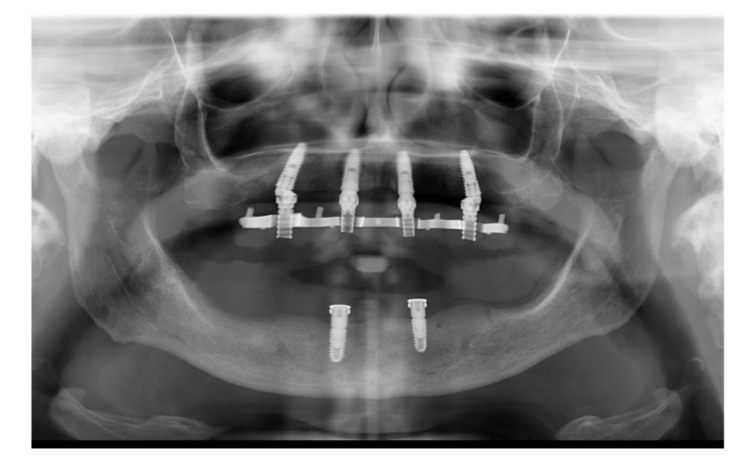

На этом этапе все последующие шаги, от планирования имплантации до доставки окончательных реставраций, были выполнены полностью в цифровом формате. После изготовления новых протезов пациенту был выполнен КТ-сканирование верхней и нижней челюстей по модифицированной технике двойного сканирования. Для последнего на нижнем протезе были применены трехмерные композитные маркеры, а для разделения зубных дуг использован восковый прикус. После этого было выполнено второе сканирование только нижнего протеза с использованием интраорального сканера (Medit i500). В нижней челюсти были запланированы два прямых импланта (Рисунок 4) и установлены (Рисунки 5 и 6) для удержания классического надпротеза.

В верхней челюсти было запланировано четыре имплантата по протоколу All-on-4 (Рисунок 7), чтобы поддерживать фиксированный, винтовой, зубной протез. Кроме того, также было запланировано уменьшение костной ткани верхней челюсти на три-четыре мм.

В день операции, после поднятия лоскута, была выполнена редукция кости с использованием базовой части хирургического шаблона в качестве ориентира (Рисунок 10). Затем были установлены два прямых передних имплантата и два наклонных задних имплантата в соответствии с протоколом All-on-4, используя имплантационную часть, без металлических втулок (Рисунок 11).